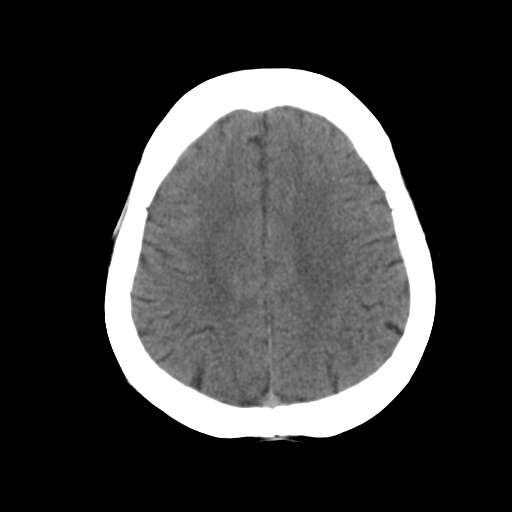

一台GE CT机突然出现下图伪影,请问是何原因?

并不是一直都有此伪影

这是设备原因造成的伪影一种伪影,

需要重新校准,

若不能矫正的话,那就没什么好办法了,

除非换配件

是不是原配球管啊,我院有台机器外圈有伪影是球管原因.

这种伪影一般还有个特点

在做薄层扫面时容易出现,一般是小于5mm,

但是在做常规10mm扫面时不会出现

这种现象并非一直出现,不分时间段,球管是租赁的,可能与电源有关

你有做一套的模和空气校正吗?没做好也会出这种情况的,一样是会有时好时坏的故障出的。